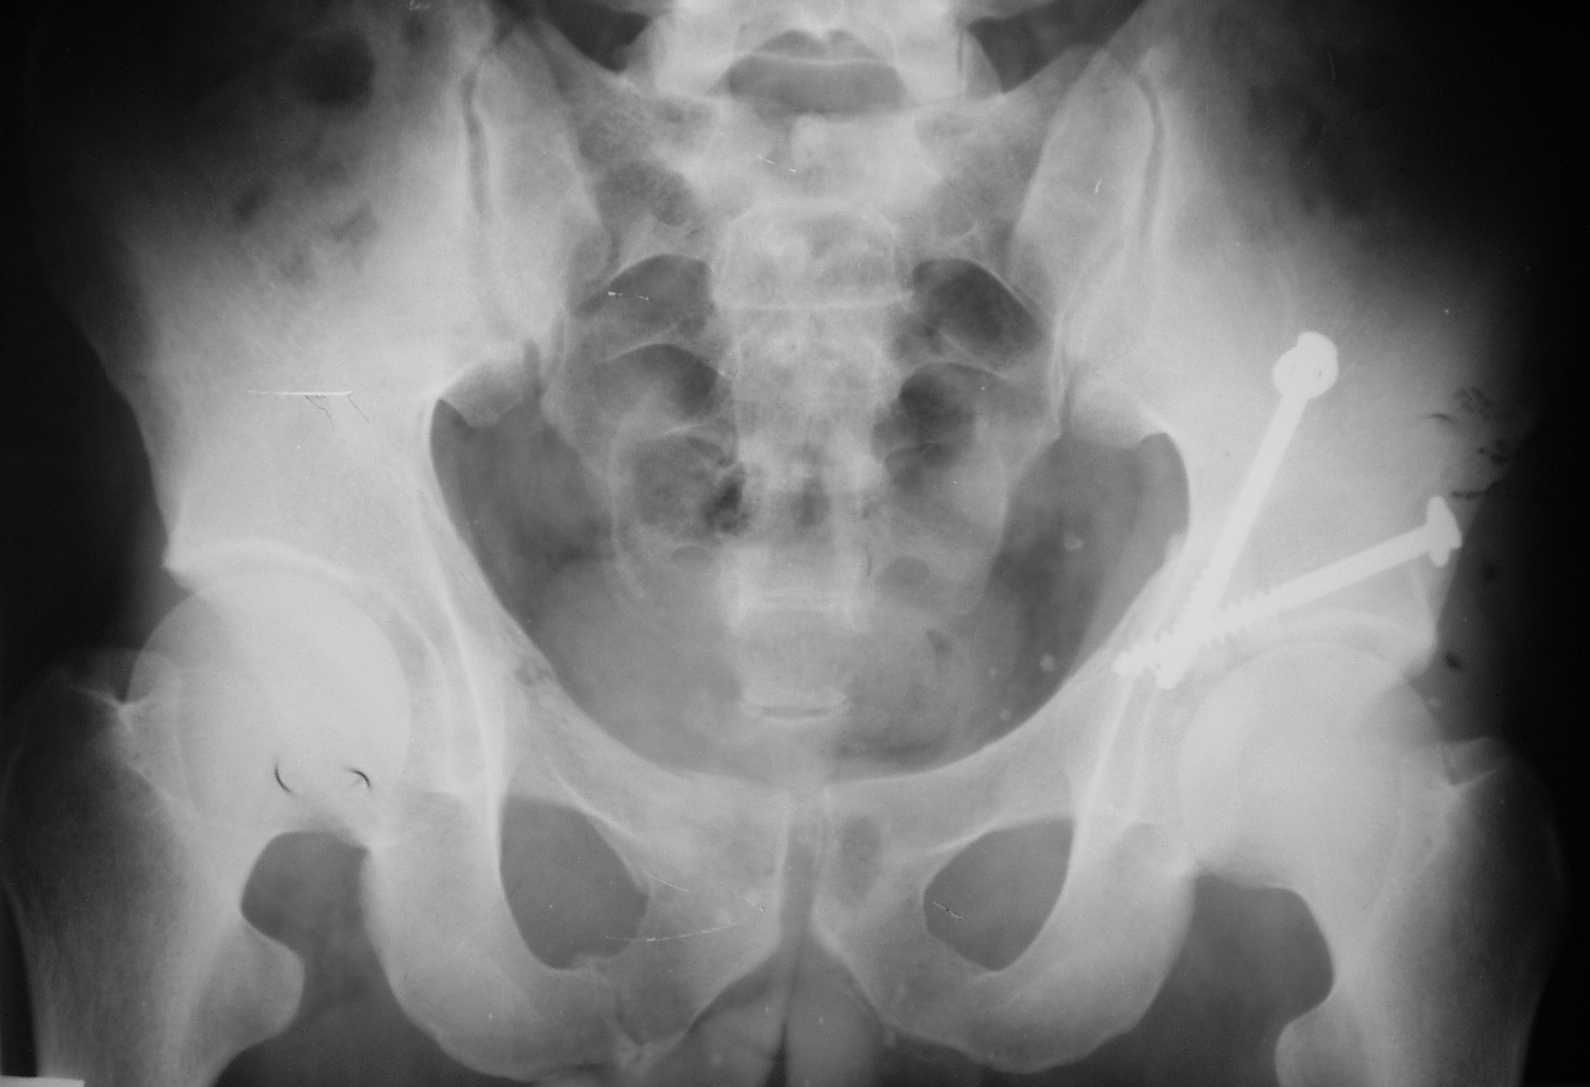

Dear dr Yordan ! I would do internal fixation as soon as possible. I sent to you one of my case with using of anterior iliofemoral approach - 5-th day after the accident. Best regards. Anatoliy Kanzyuba, MD. Donetsk Ukraine